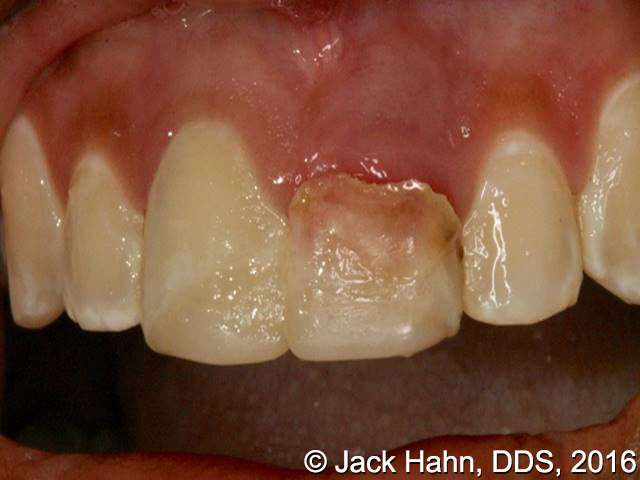

CASE #4 Trauma Case – Central Incisors Internal / External Resorption

Implants, that replace failed endo- or perio-compromised teeth, have a MUCH higher success rate with laser decontamination of the osteotomy site. LightScalpel laser surgical and perio laser tips ensure excellent access to extraction socket for the optimum removal of granulation tissue and socket decontamination (protocol involves manual curettage of the socket with alternating rinsing and lasing).

The patient, a 17-year-old female was involved in a water slide accident 3 years ago. As a result, both central incisors were avulsed and an endodontist replanted them. Both teeth exhibited internal and external resorption. Dr. Hahn extracted both central incisors, removed all the root fragments and sanitized the sites with the LightScalpel laser which also eliminated any granulation tissue. The #8 area was prepared to place a Hahn 4.3×13 Implant and #9 was prepared for a Hahn 3.5×13. 3mm tall Hahn healing abuts were placed slightly below the gingival-tissue level to help develop an emergence profile when at the restoration time in 4 months. Upon seeing the x-ray, Dr. Hahn tightened the healing abutment on #9 to be sure that it was completely seated on the implant. 45nucm. stability was achieved on both implants. He then placed some bone putty to seal any openings. To be on the safe side, he decided to place a temporary partial instead of immediate temporary prosthetics.